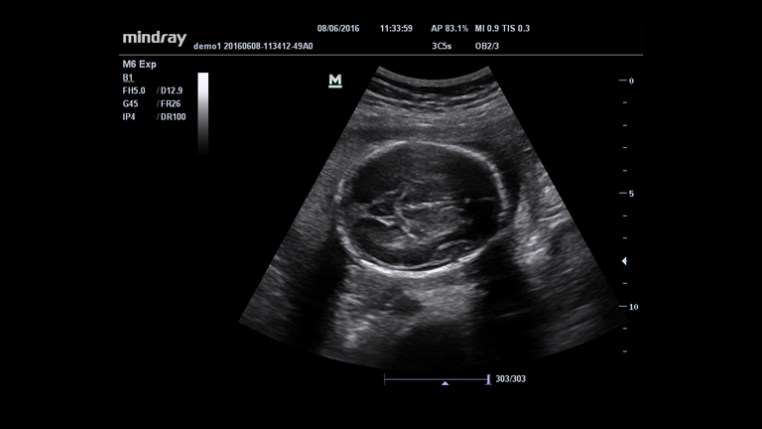

3D/4D imaging technology delivers a range of tools that help take advantage of the full value of volume data. With rich rendering modes, more information on fetus structure is made available to make a more confident diagnosis.

Auto measurement of fetal parameters:trace and calculate the BPD,OFD,HC,AC and FL on a single click.